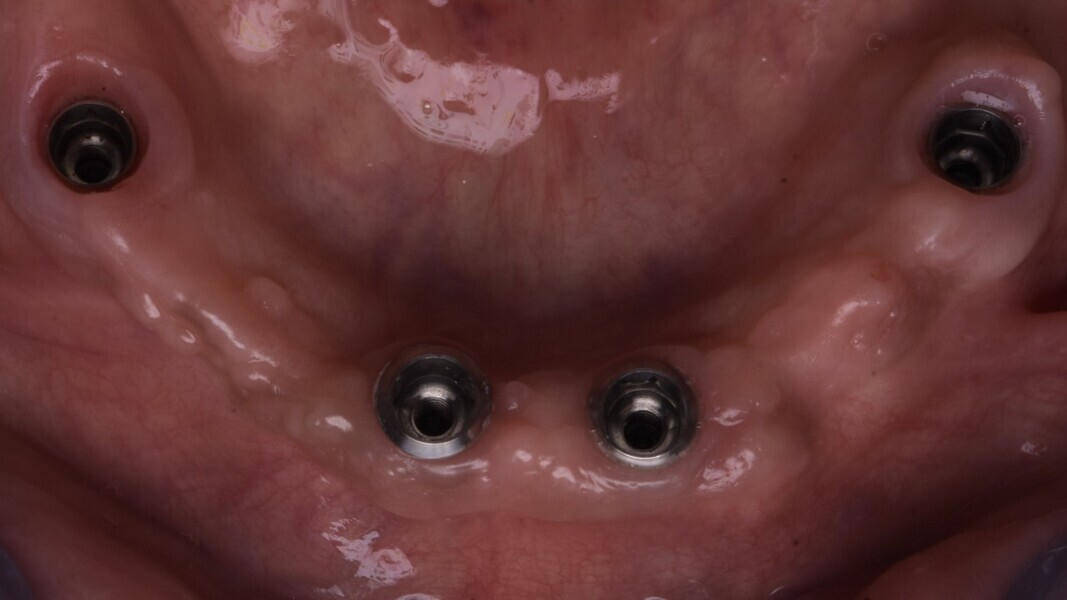

Au niveau mandibulaire (Fig. 14), la cicatrisation mandibulaire de la gencive autour des implants tissue levels est optimale. Nous ne recherchons pas une mise en condition gingivale particulière car à la mandibule la pérennité s’inscrira dans une hygiène adaptée, et donc nous allégeons volontairement l’intrados, afin d’optimiser le passage des brossettes par le patient